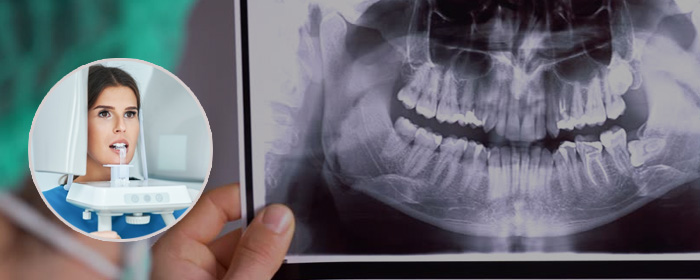

Digital X-rays (Intra & Extra Oral View)

A digital X-ray, or digital radiography, is a modern type of X-ray that utilises digital sensors instead of photographic film, as with a traditional X-ray. The image captured is converted to digital data immediately and is available for review within seconds.

Digital X-rays are of particular interest in dentistry, where the rapid availability of the results means that a dentist can enhance the images by controlling the exposure in real time and therefore can obtain clear and detailed results that can be shared with the patient immediately. The clarity of digital X-rays makes them superior to traditional X-rays in terms of finding tiny fractures and imperfections in the teeth.

Intra Oral & Extra Oral X-rays

There are two main types of dental X-rays:

• Intraoral: The film or sensor is inside your mouth. Intra-oral photos are photos that are taken of your teeth, gums and oral tissue. These photos may be of a single tooth, a group of teeth, or any area of your mouth. At our office, photos are taken with a small, high quality digital camera that moves comfortably within your mouth

• Extraoral: The film or sensor is outside your mouth.